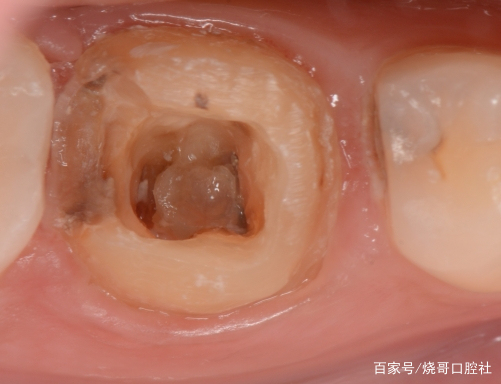

如何判斷牙齒牙洞已經(jīng)深入到牙髓?,牙齒牙洞深度判斷,如何確定已影響牙髓?

1、口腔鏡檢查:通過口腔鏡檢查,可以清晰地觀察到牙齒表面的牙洞以及牙洞內的情況,醫(yī)生可以判斷牙洞是否已深入牙髓,并評估病情嚴重程度。